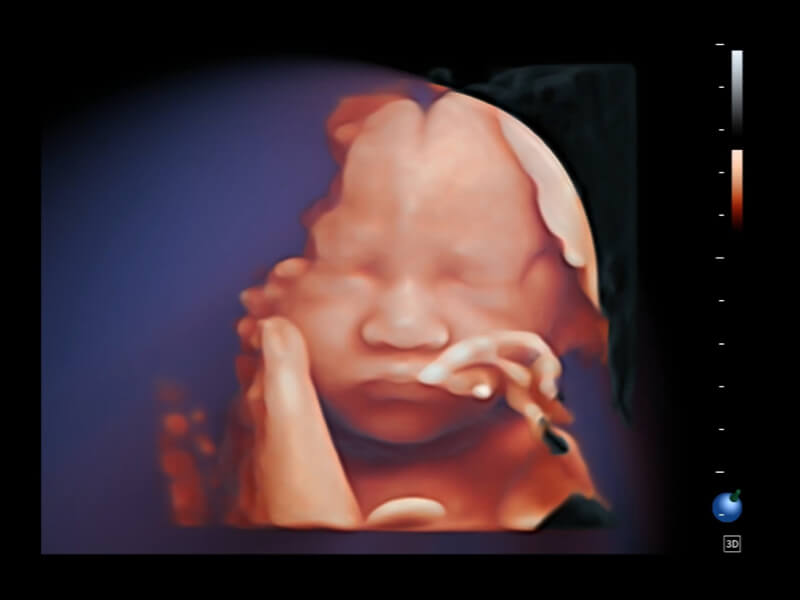

作為開立醫(yī)療全新打造的超高端旗艦超聲產(chǎn)品,從探頭抬起喚醒開啟掃查到多維探頭發(fā)射接收,通過先進(jìn)的場(chǎng)成像發(fā)射、自適應(yīng)聚合重建等技術(shù),基于RF Data原始射頻數(shù)據(jù)在圖像生成、高端功能等方面實(shí)現(xiàn)突破,為婦產(chǎn)科、兒科提供全方位臨床解決方案。

夢(mèng)溪?P80以“關(guān)愛女性”為基石,提供全方位的解決方案,量身定制以滿足女性的健康需求,涵蓋婦科、生殖健康檢查、產(chǎn)前篩查及產(chǎn)后康復(fù)等領(lǐng)域。